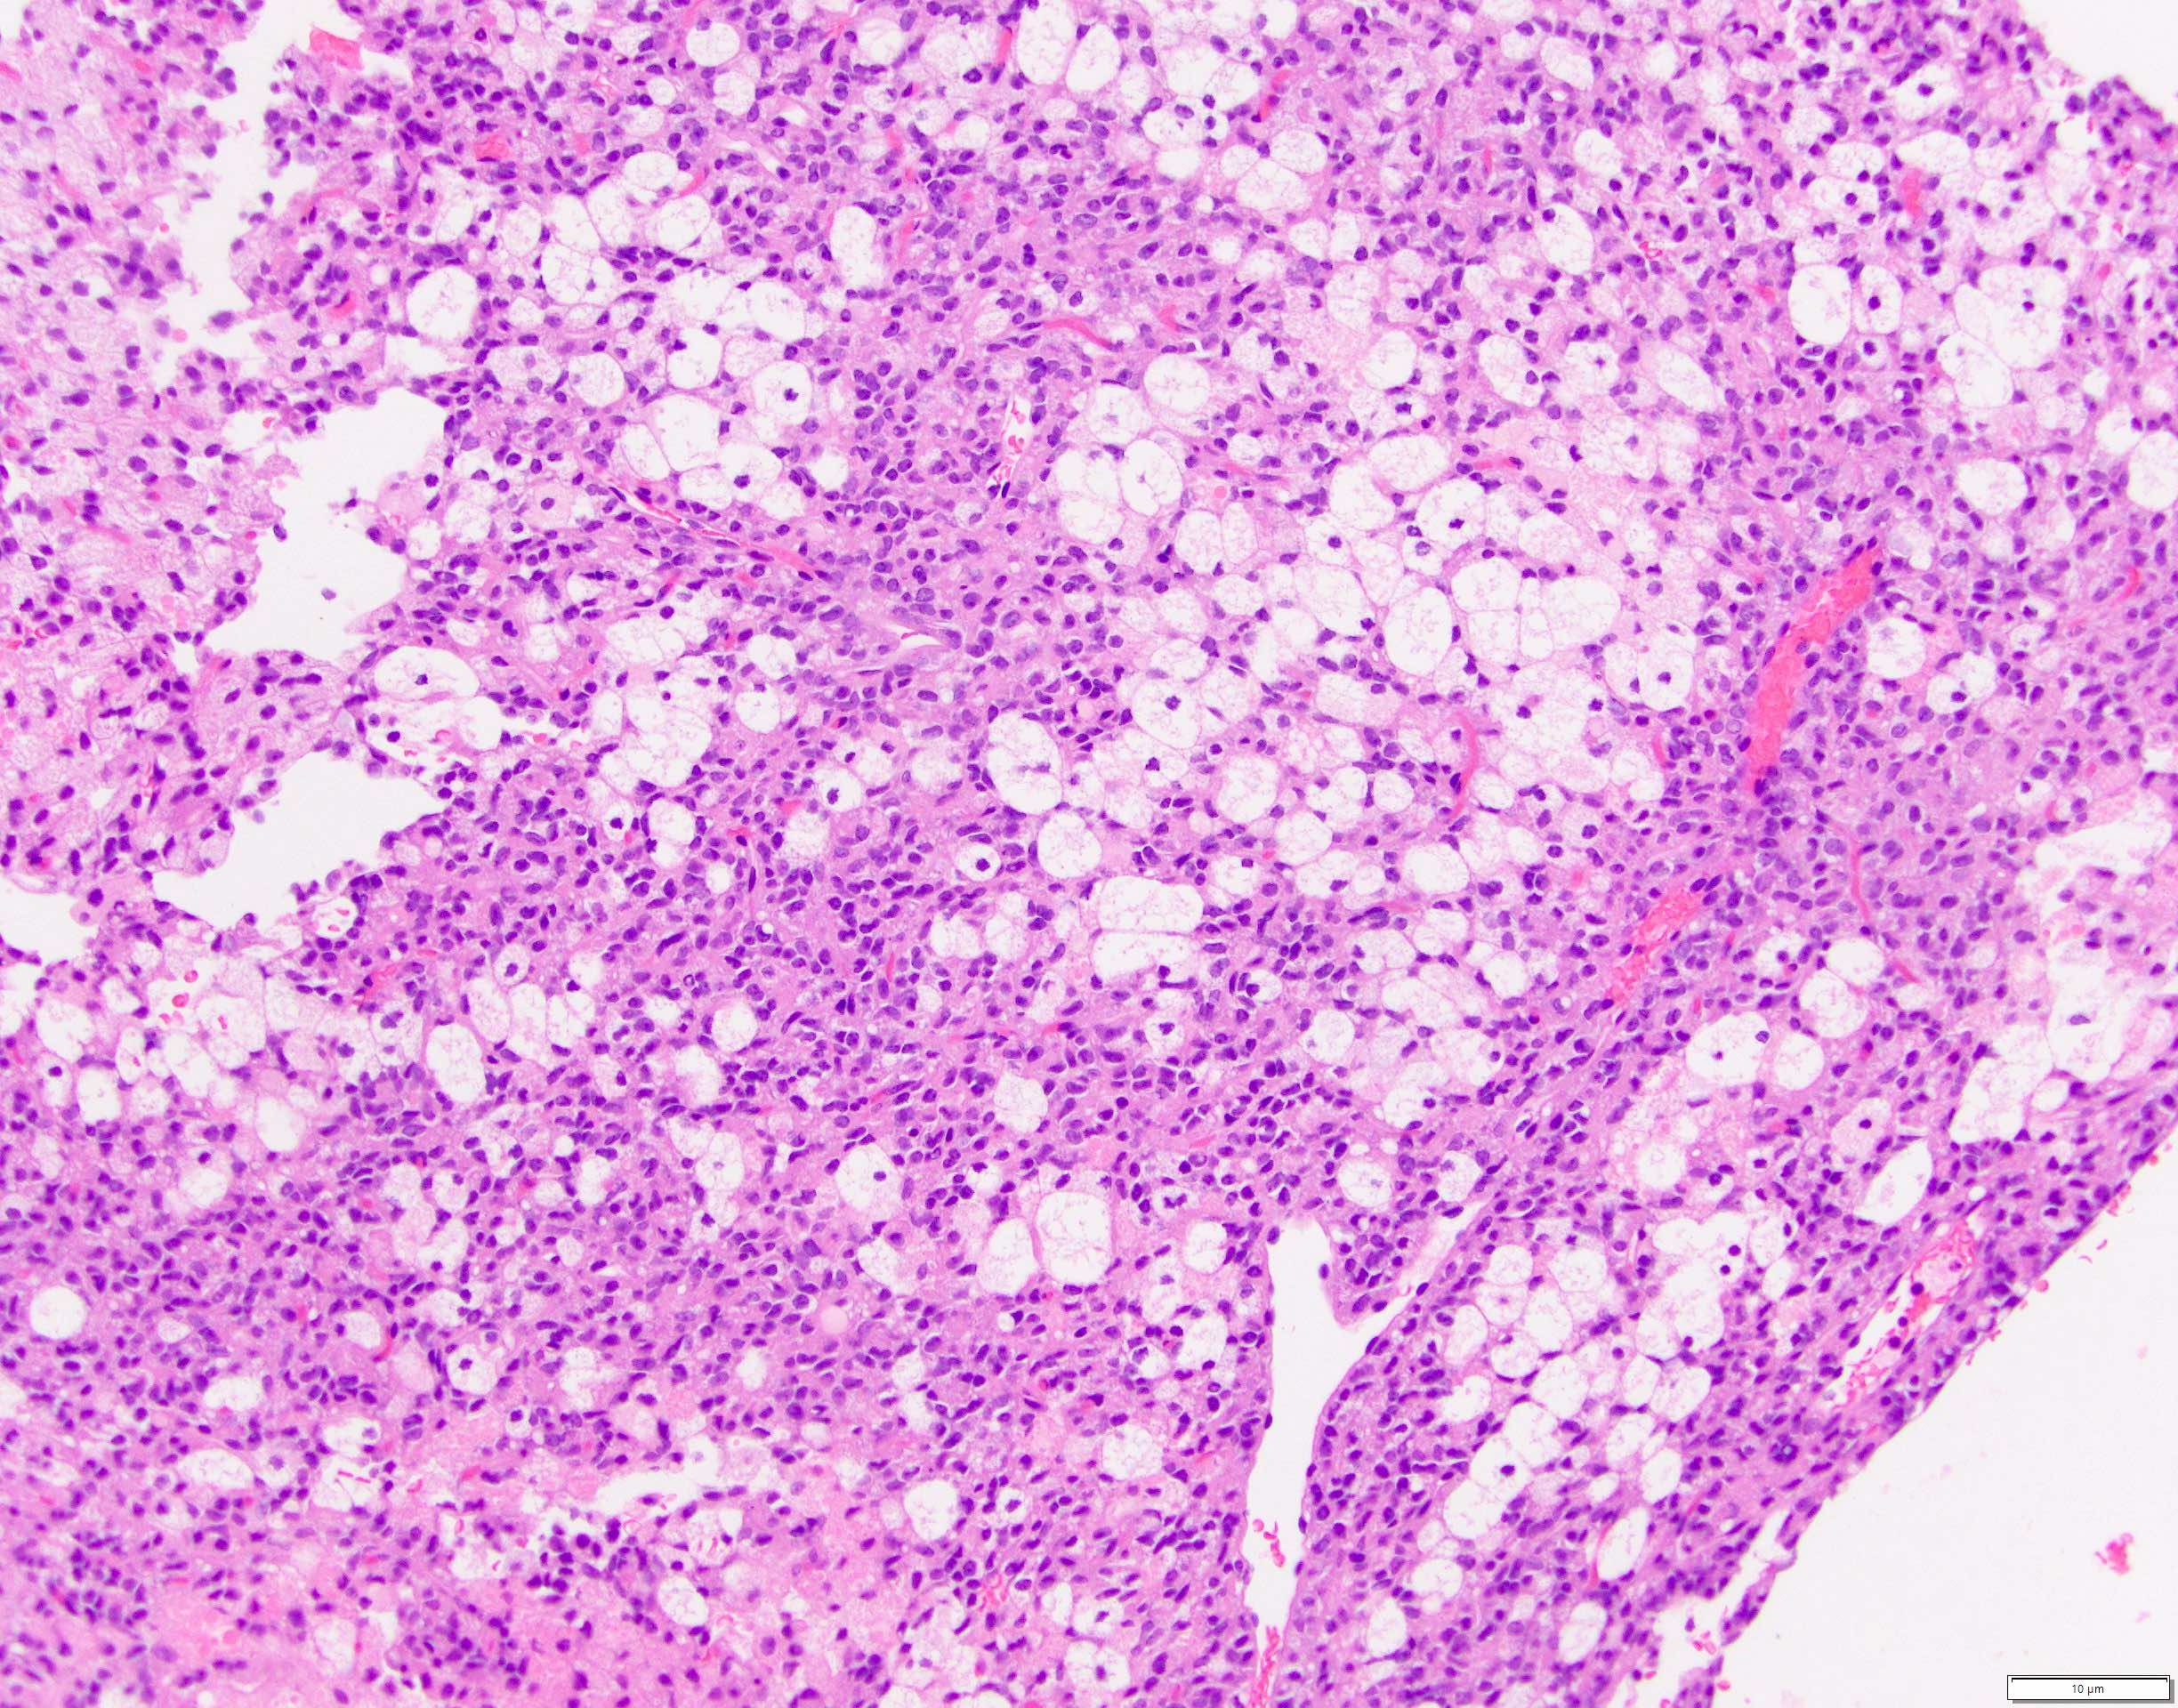

Microscopic (histologic) description

- Tumors are heterogeneous, with variable admixture of solid and pseudopapillary areas

- Solid areas are comprised of uniform cells admixed with capillary sized blood vessels

- Pseudopapillae are formed due to tumor cells getting detached from blood vessels forming fibrovascular stalks or rosette-like structures (Arch Pathol Lab Med 2020;144:829)

- Stroma usually shows various degrees of hyalinization or evidence of degeneration, such as hemorrhage, foamy macrophages, calcification and cholesterol clefts

- Tumor cells usually have a moderate amount of eosinophilic cytoplasm with intracytoplasmic hyaline globules (PAS+ and diastase resistant, positive for alpha-1-antitrypsin) and perinuclear vacuoles (Am J Surg Pathol 2011;35:981)

- Relatively uniform nuclei with finely textured chromatin, inconspicuous nucleoli and characteristic longitudinal grooves

- Variants include clear cell, oncocytic and pleomorphic

- Rare mitotic figures

- Although grossly well circumscribed, microscopic finding of infiltration to the surrounding pancreatic tissue is not uncommon

- Rare cases of highly aggressive behavior; histological features in those cases included diffuse growth pattern, extensive necrosis, significant nuclear atypia, high mitotic count (35 - 70/50 high power fields) or sarcomatoid features (Am J Surg Pathol 2005;29:512)

Microscopic (histologic) images

Contributed by Monika Vyas, M.D., Omid Savari, M.D. and Raul S. Gonzalez, M.D.